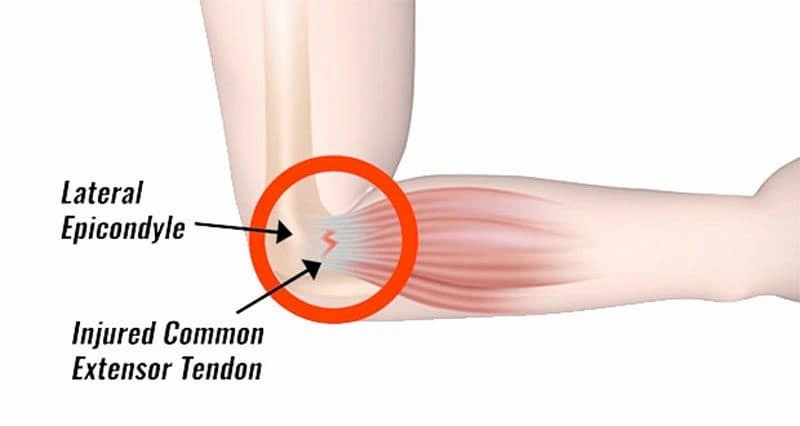

- A patient may have had prior or current tendinitis or tendinosis or partial thickness tear of the rotator cuff muscles of the shoulder.